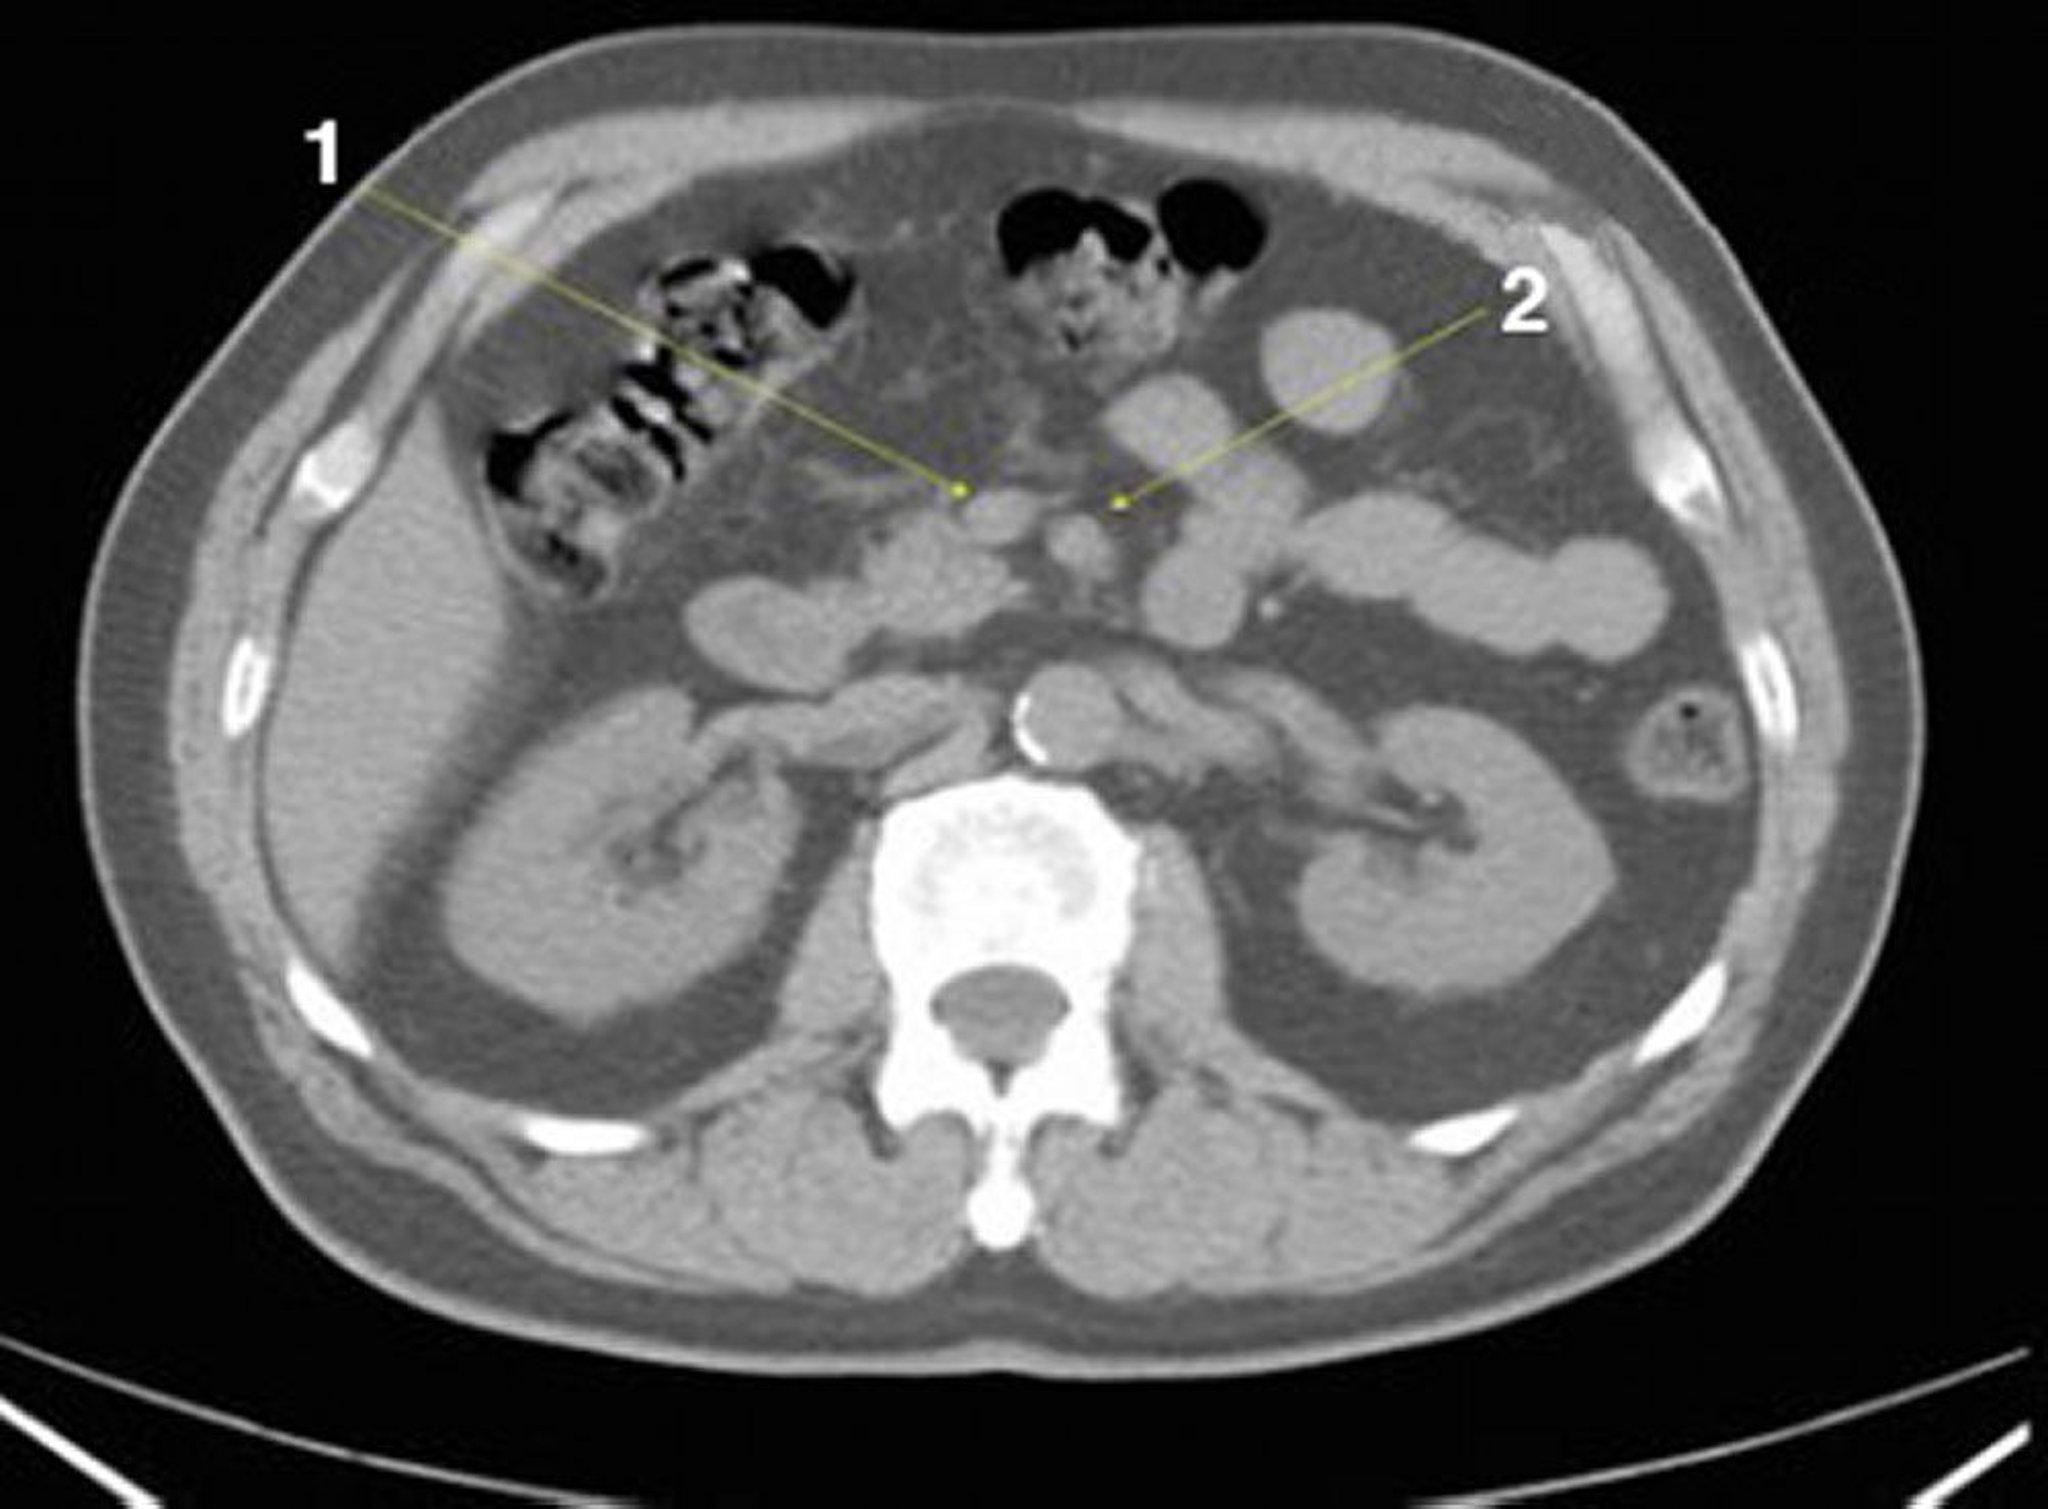

Phim chụp CT vùng bụng và vùng chậu không thuốc cản quang cho thấy giải phẫu bình thường (lát cắt 13)

1 = tĩnh mạch mạc treo tràng trên; 2 = động mạch mạc treo tràng trên.